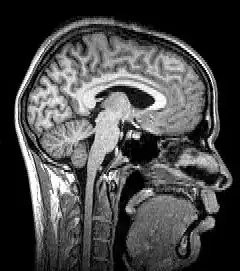

Para-sagittal MRI of the head in a patient with benign familial macrocephaly

Structural magnetic resonance imaging (structural MRI) of a head, from top to base of the skull

Sagittal MRI slice at the midline

Magnetic resonance imaging (MRI) uses magnetic fields and radio waves to produce high quality two- or three-dimensional images of brain structures without the use of ionizing radiation (X-rays) or radioactive tracers.